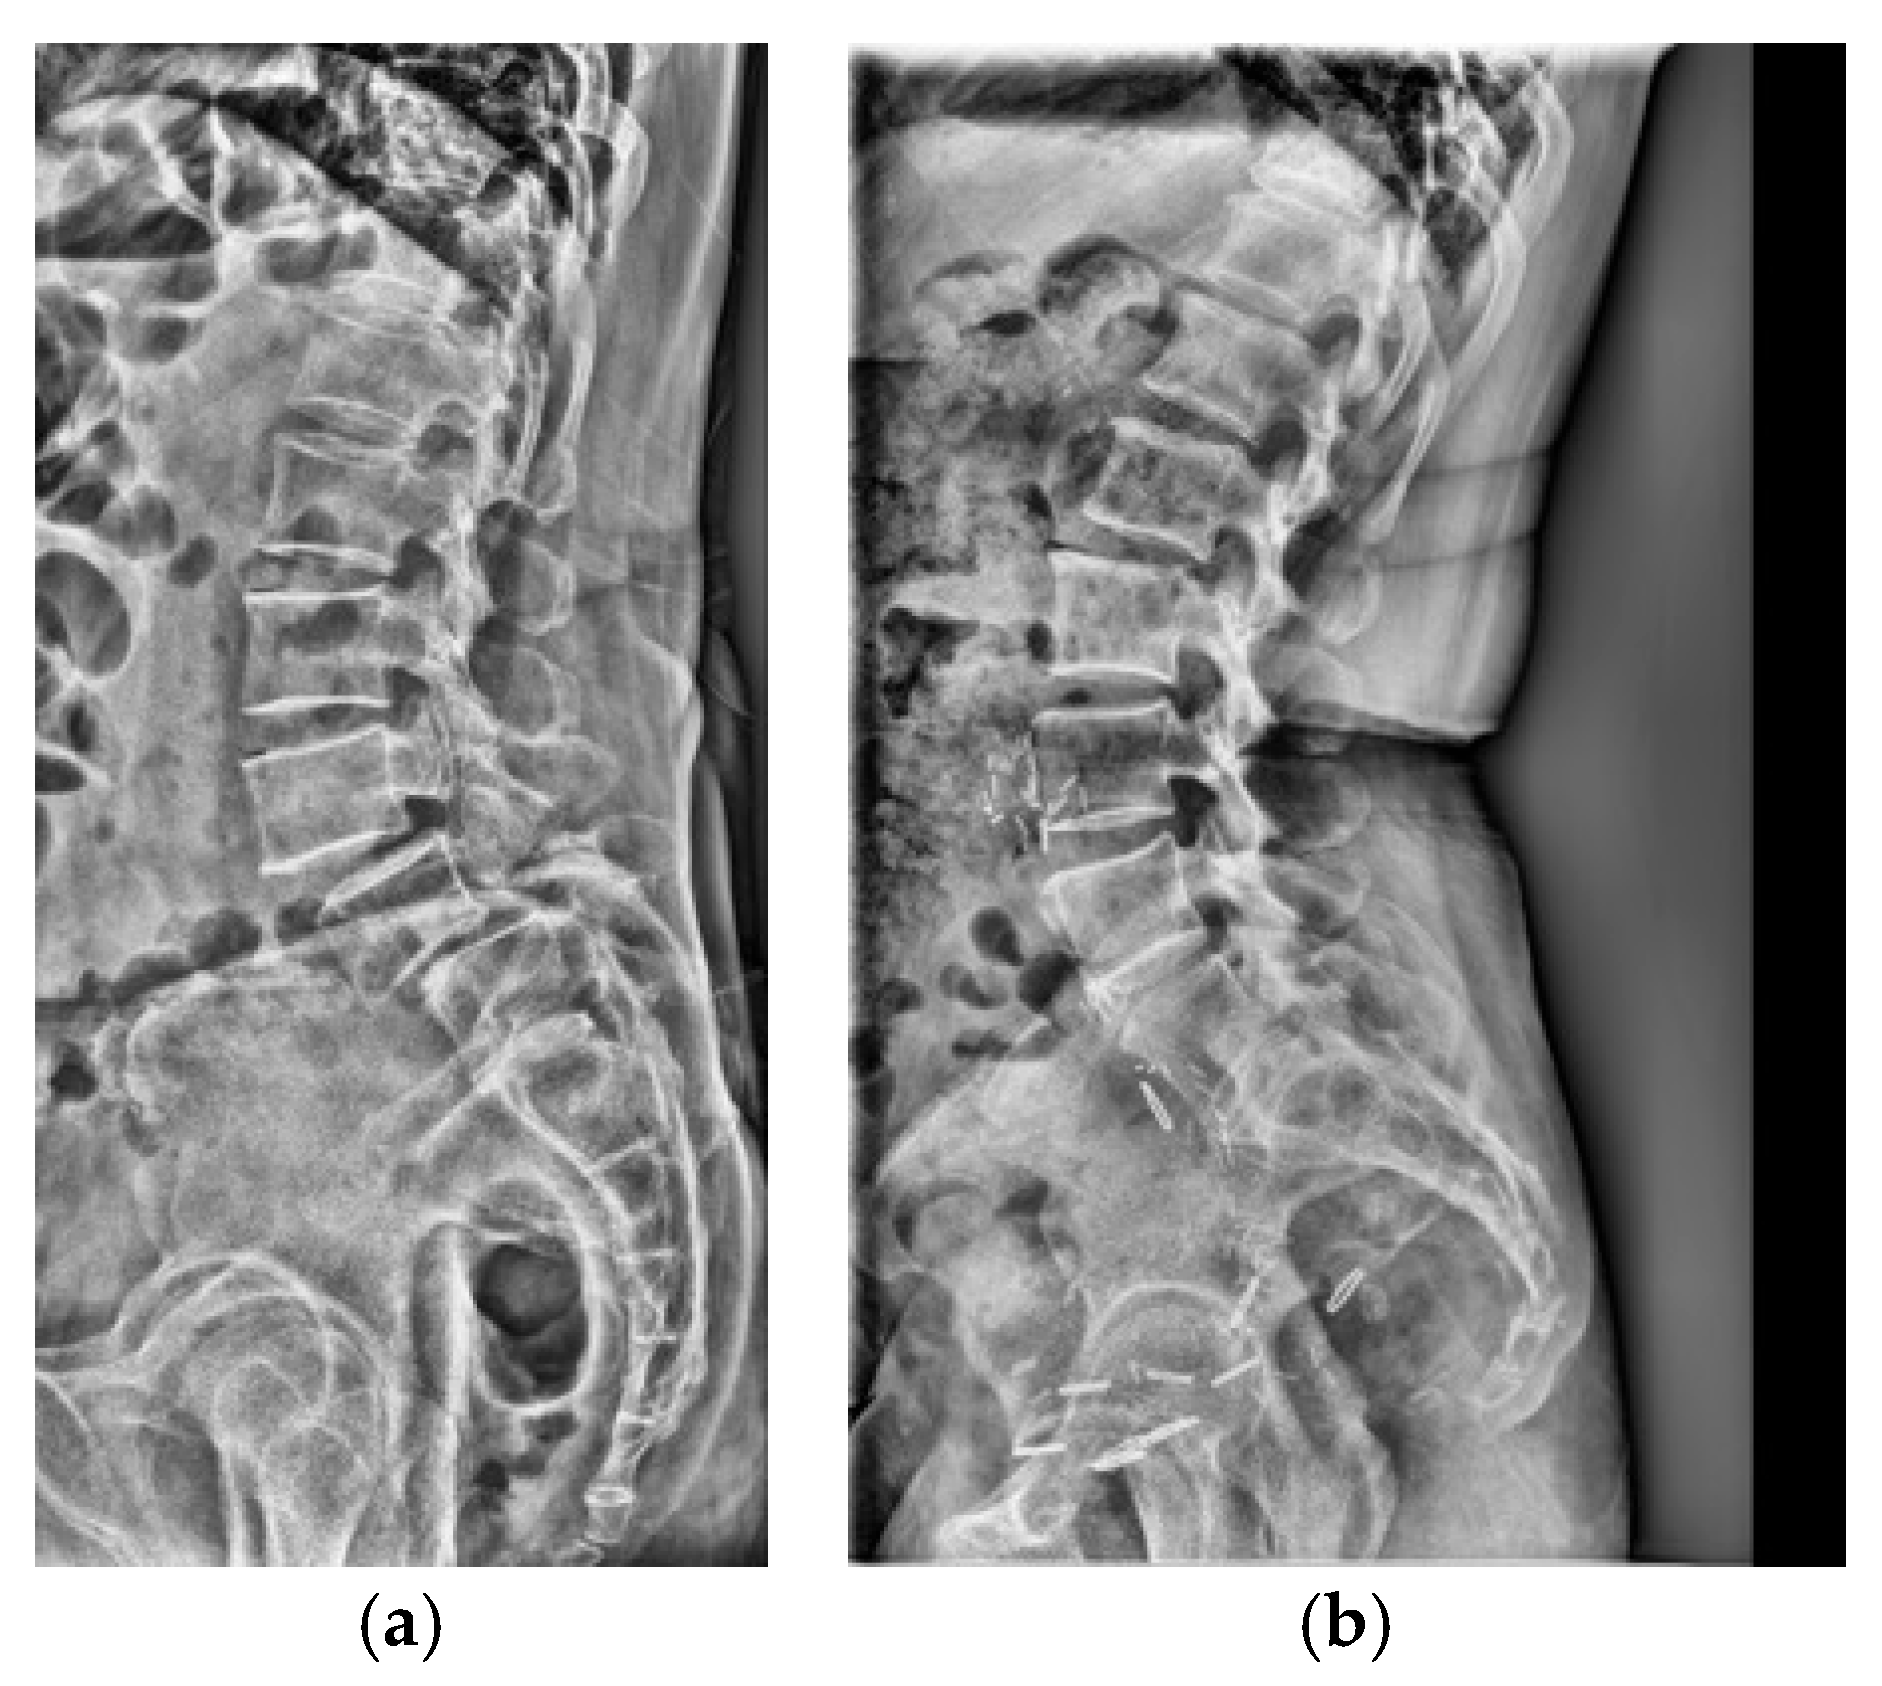

Adult patients (≥18 years) who underwent standing lumbar lateral radiography at a single tertiary hospital between January 2010 and November 2023 were included for this retrospective study. All standing lumbar lateral radiographs were acquired using digital radiography systems from multiple manufacturers, including Philips Healthcare (Amsterdam, The Netherlands), Canon Medical Systems Corporation (Ōtawara, Tochigi, Japan), Samsung Electronics Co., Ltd. (Suwon, Republic of Korea), and Fujifilm Corporation (Tokyo, Japan). To establish a definitive ground truth, only patients for whom the presence or absence of LSTV could be unequivocally determined using whole-spine MRI, CT, or radiographs that allowed for accurate vertebral enumeration were selected. The presence or absence of LSTV was labeled based on the MRI conclusion that explicitly mentioned transitional vertebra, lumbarized, sacralized, lumbarization, or sacralization. Patients were excluded if they had a history of lumbar surgery with instrumentation, severe spinal deformities or pathologies obscuring local anatomy, or poor image quality (Figure 1a). The final dataset was stratified, with 10% reserved as an independent test set and the remaining 90% subjected to stratified 5-fold cross-validation for model development and validation. Representative examples of each class are shown in Figure 1b,c, illustrating the visual differences between LSTV cases and normal lumbosacral anatomy. These examples highlight the morphological variability that makes manual identification challenging.

Three deep learning architectures were evaluated for model development: DINOv2-base, CLIP (ViT-B/32), and ResNet-50. For the DINOv2 and CLIP models, the vision encoder was frozen, and only the classification head—consisting of a single hidden layer (512 units) and a final output layer—was trained. For the ResNet-50 model, the first two convolutional blocks were frozen, and the remaining layers were fine-tuned. All models were trained with label smoothing (0.1) and dropout regularization (0.3–0.4). Input radiographs were resized to 224 × 224 pixels, normalized using ImageNet mean and standard deviation, and augmented through random rotation, horizontal flipping, and contrast-limited adaptive histogram equalization (CLAHE) (Figure 2).

Figure 1. (a) Flow diagram of patient selection and dataset partitioning. Adult patients (≥18 years) with standing lumbar radiographs and MRI/CT-confirmed LSTV were included (n = 3116; 1941 LSTV, 1175 normal) and divided into training (n = 2803) and independent test (n = 313) sets. (b) Representative lateral radiograph showing LSTV with lumbarization of the S1 vertebra and morphological alteration of the L5–S1 junction. (c) Representative radiograph of a normal lumbar spine illustrating a well-defined lumbosacral junction and distinct separation between the L5 vertebra and sacrum.